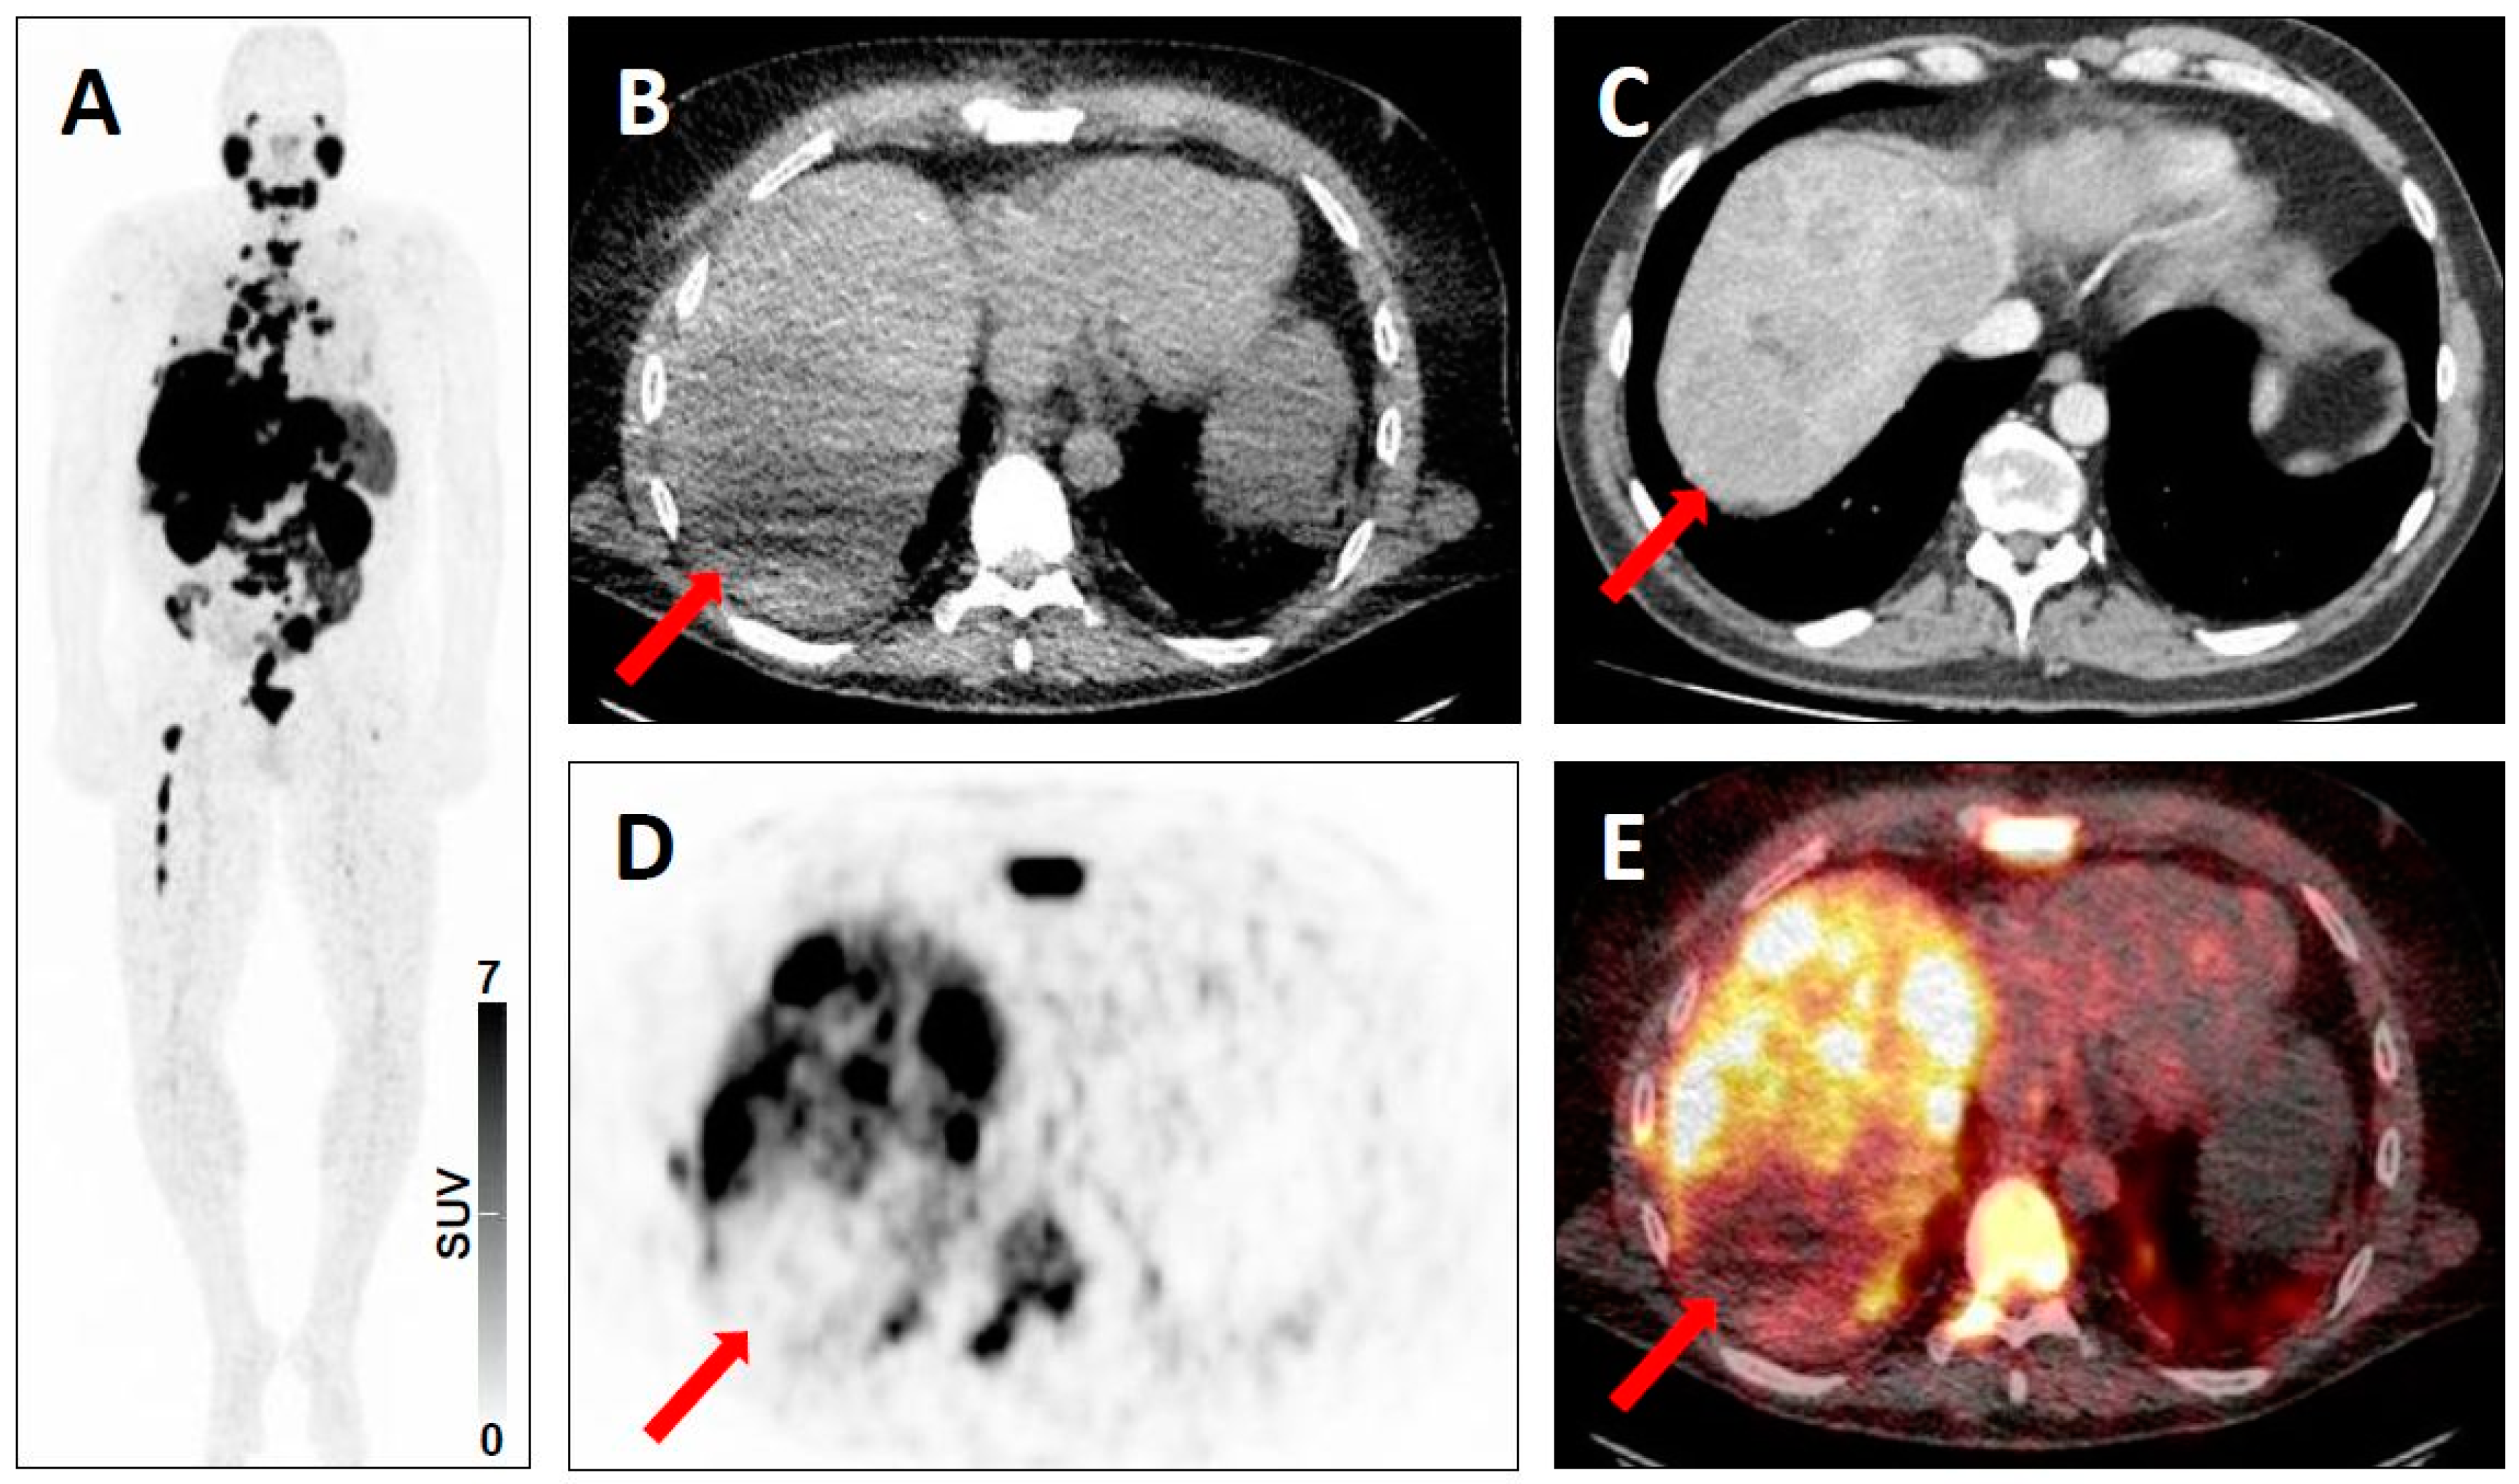

| 3 | 3A | - Regional lymph nodes, e.g. low-level uptake in mesenteric lymph node in midabdomen [20] - Mild radiotracer uptake in a supraclavicular lymph node [5] | - Pelvic lymph node involvement with low-level uptake [19] |

| 3C | - Intense breast uptake on SSTR-PET [20,21] - Intense uptake in the Musculus vastus lateralis [18] | - High level of radiotracer uptake in a lung nodule in a patient with low level of serum prostate-specific antigen [19] - Substernal thyroid nodule with radiotracer uptake (and without further work-up) [21,72] | |